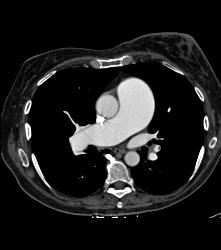

Diagnosis

Bicuspid Valve